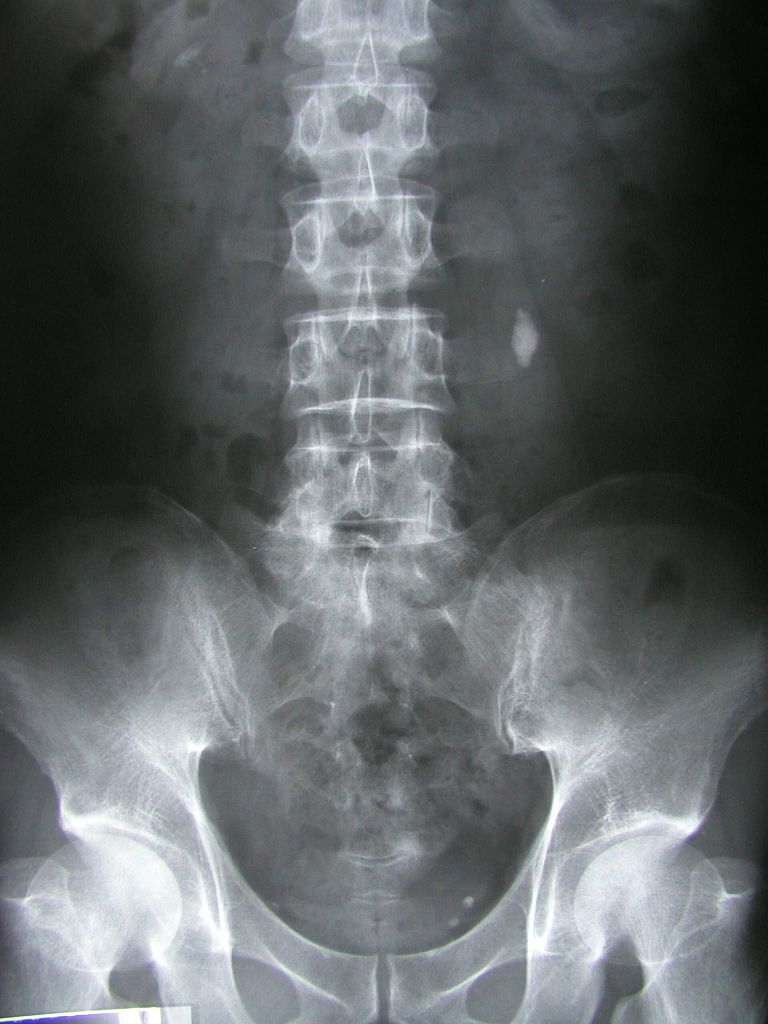

In most cases ABSOLUTELY NOT. And this is because the majority of imaging only shows normal age related changes. And the medical community is finally starting to acknowledge that these findings they used to associate with sciatica generally do not matter. In less than 5% of back pain related cases is imaging of the spine actually indicated (based on physical exam findings). And this is Excellent news for anyone with back pain or sciatica.